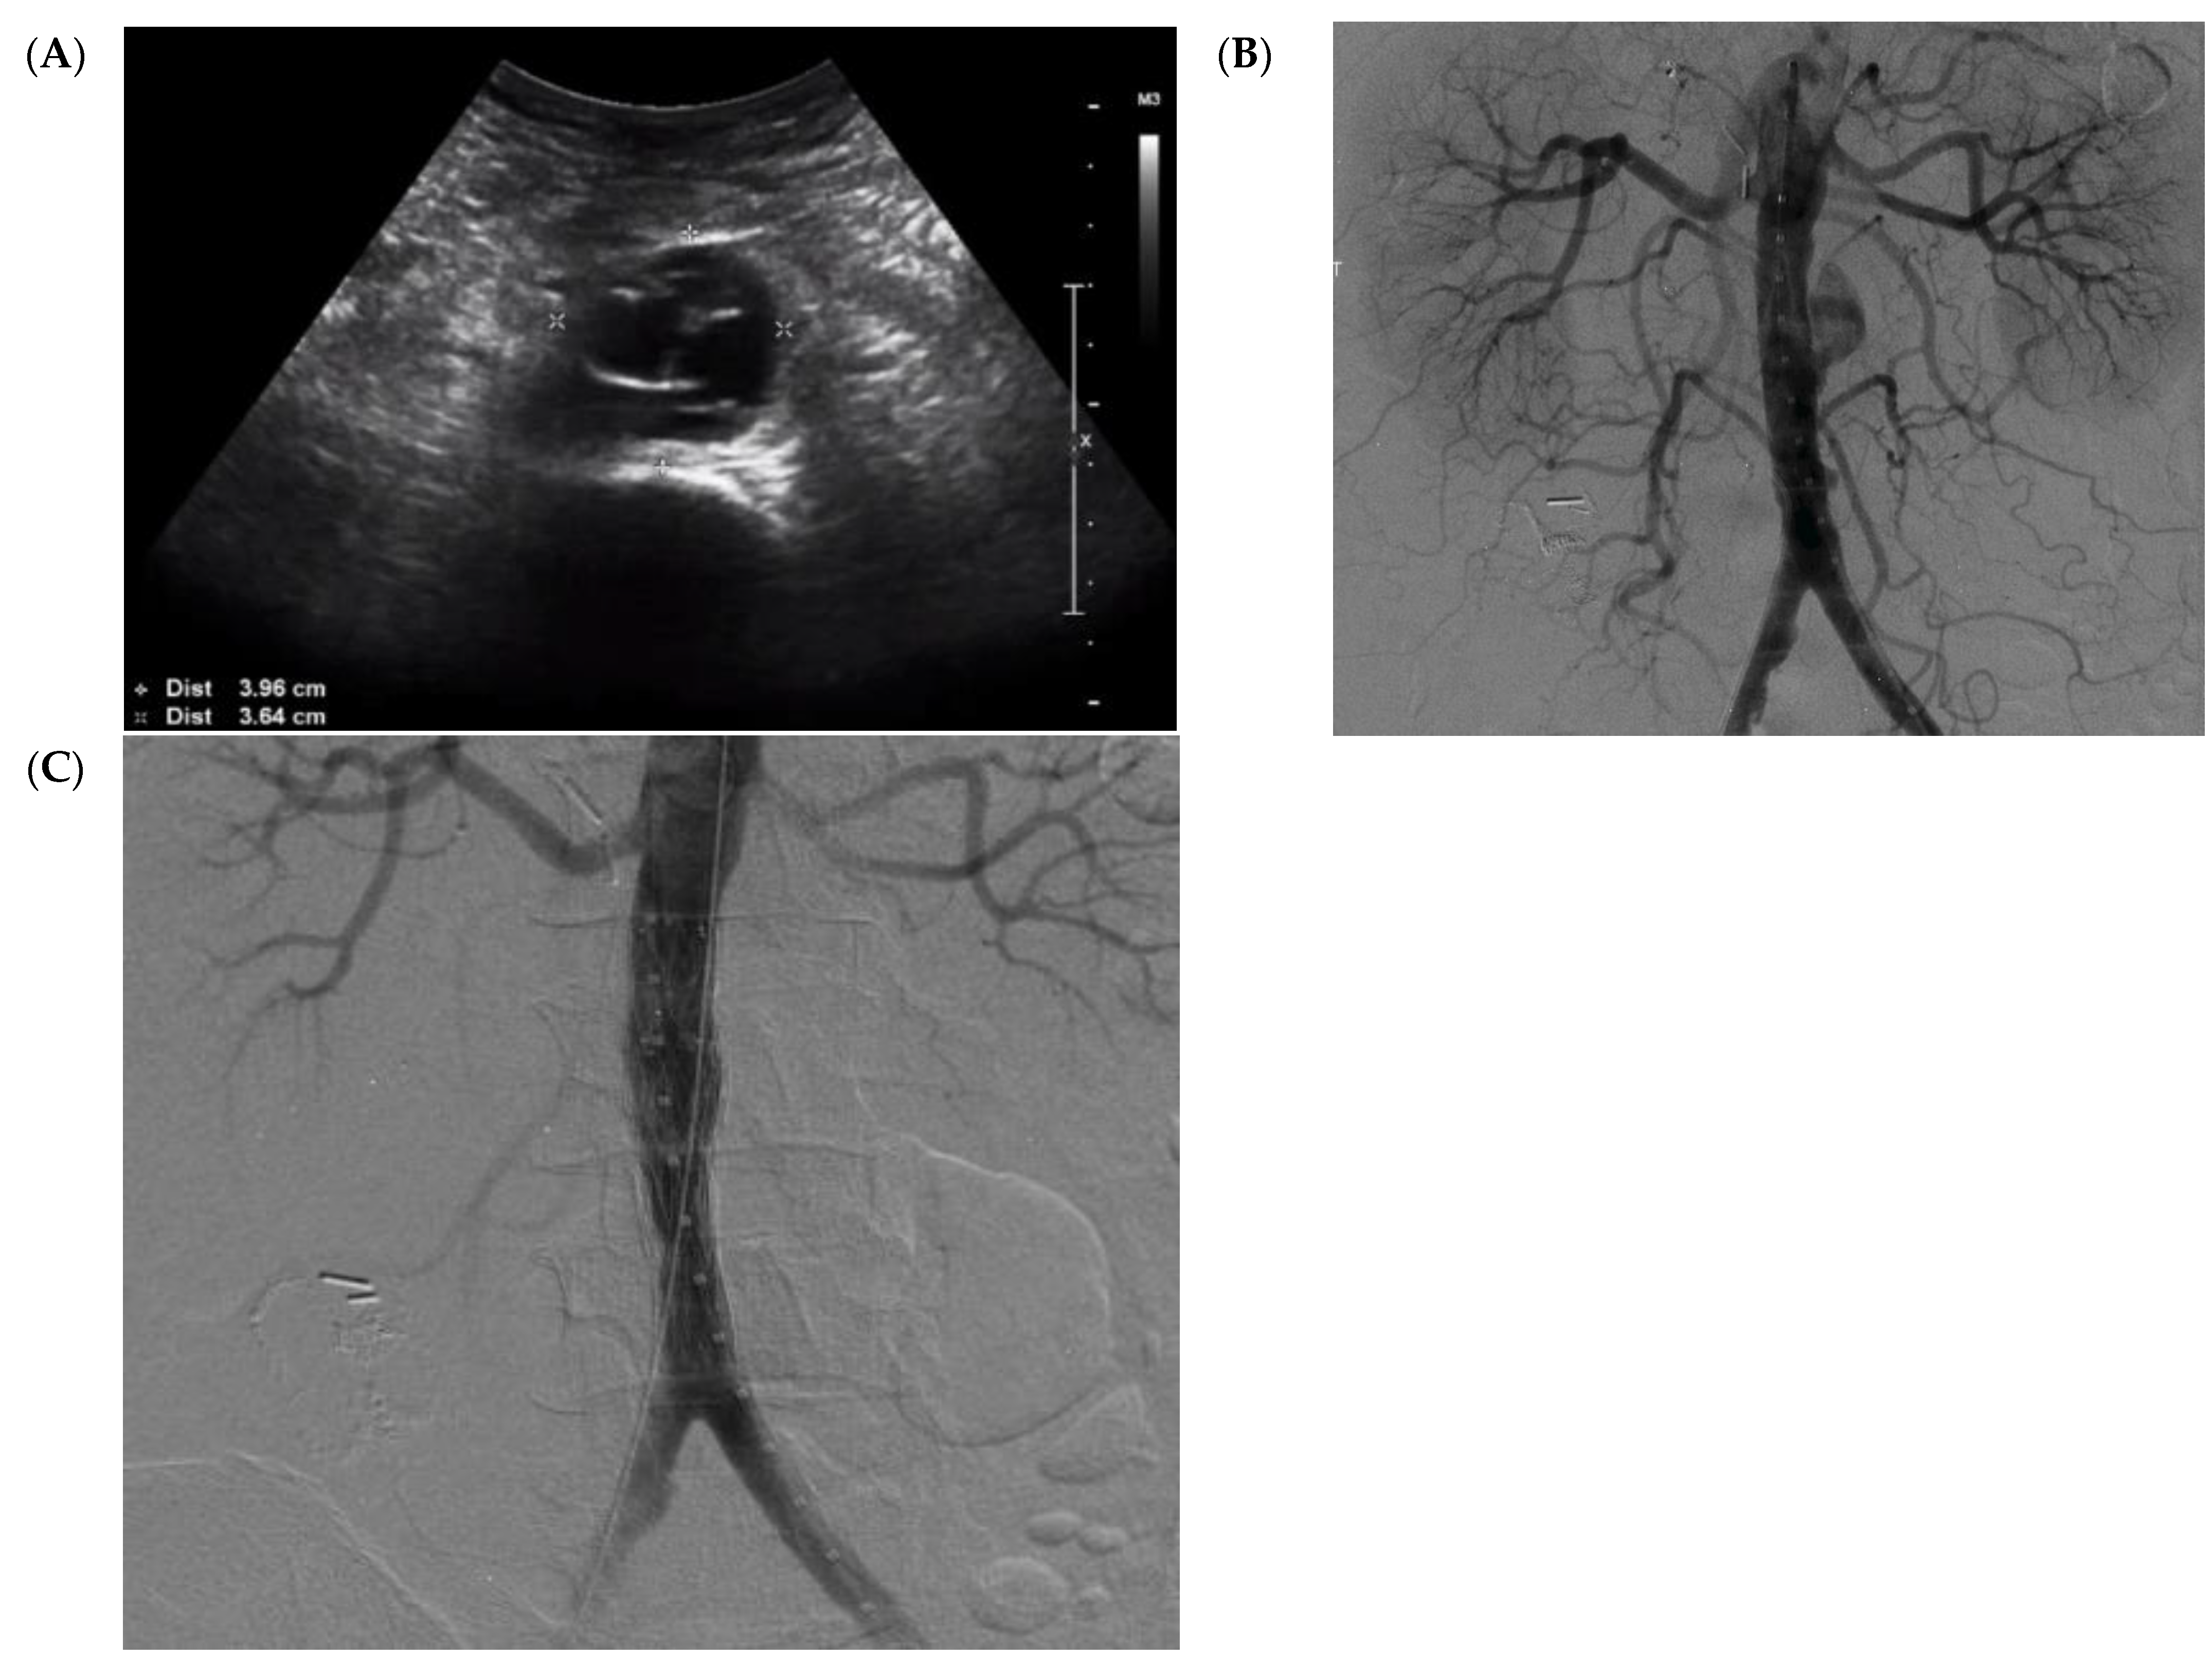

2. Case Report